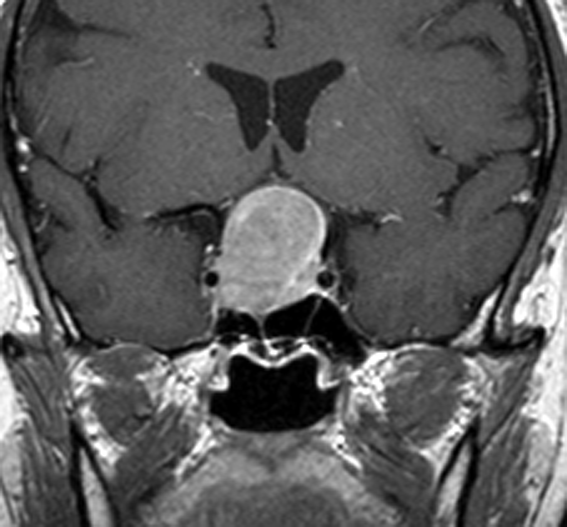

典型的なMRIの画像です

下垂体腺腫のMRIです。両側の視野障害(両耳側半盲)のために手術を受けた患者さんのものです。この腫瘍は非機能性腺腫といってホルモンを出さない腫瘍でした。少し大きめでしたが全部取れて視野の障害はよくなりました。

左の2枚はガドリニウム造影剤を使って写したもので腫瘍の形がよくわかります。右の1枚はT2強調画像と言います。MRIでは撮影の仕方によって見え方が違います。

中央は手術前の下垂体腺腫で,視神経も正常下垂体も位置はわかりません。

右は手術翌日の画像です。黄色の矢印の先が残した正常下垂体組織です。桃色の矢印の先に視神経(視交叉)がはっきり見えています。術後の一時的な尿崩症がありました。クモ膜が残っているので髄液漏は生じませんでした。でも正常下垂体組織(黄色矢印)も視交叉も腫瘍に圧迫されてペラペラになっていますから,いつもうまく行くとは限りません。